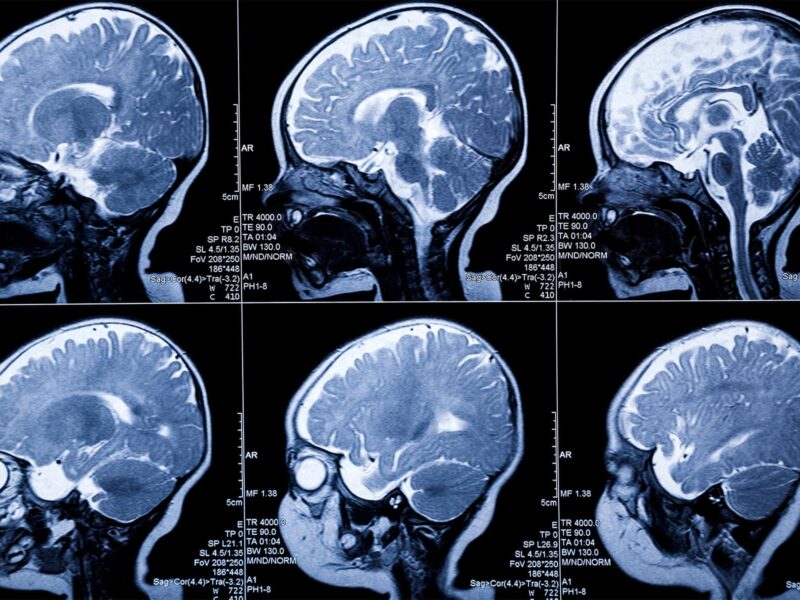

New MRI Technique Might Help Spot MS Sooner

By Cara MurezHealthDay Reporter FRIDAY, Jan. 7, 2022 (HealthDay News) – Researchers in Austria say a new MRI technique may lead to faster diagnosis and treatment for people with multiple sclerosis. The technique can detect biochemical changes in the brains of people with MS early in their disease, according to findings published Jan. 4 in […]